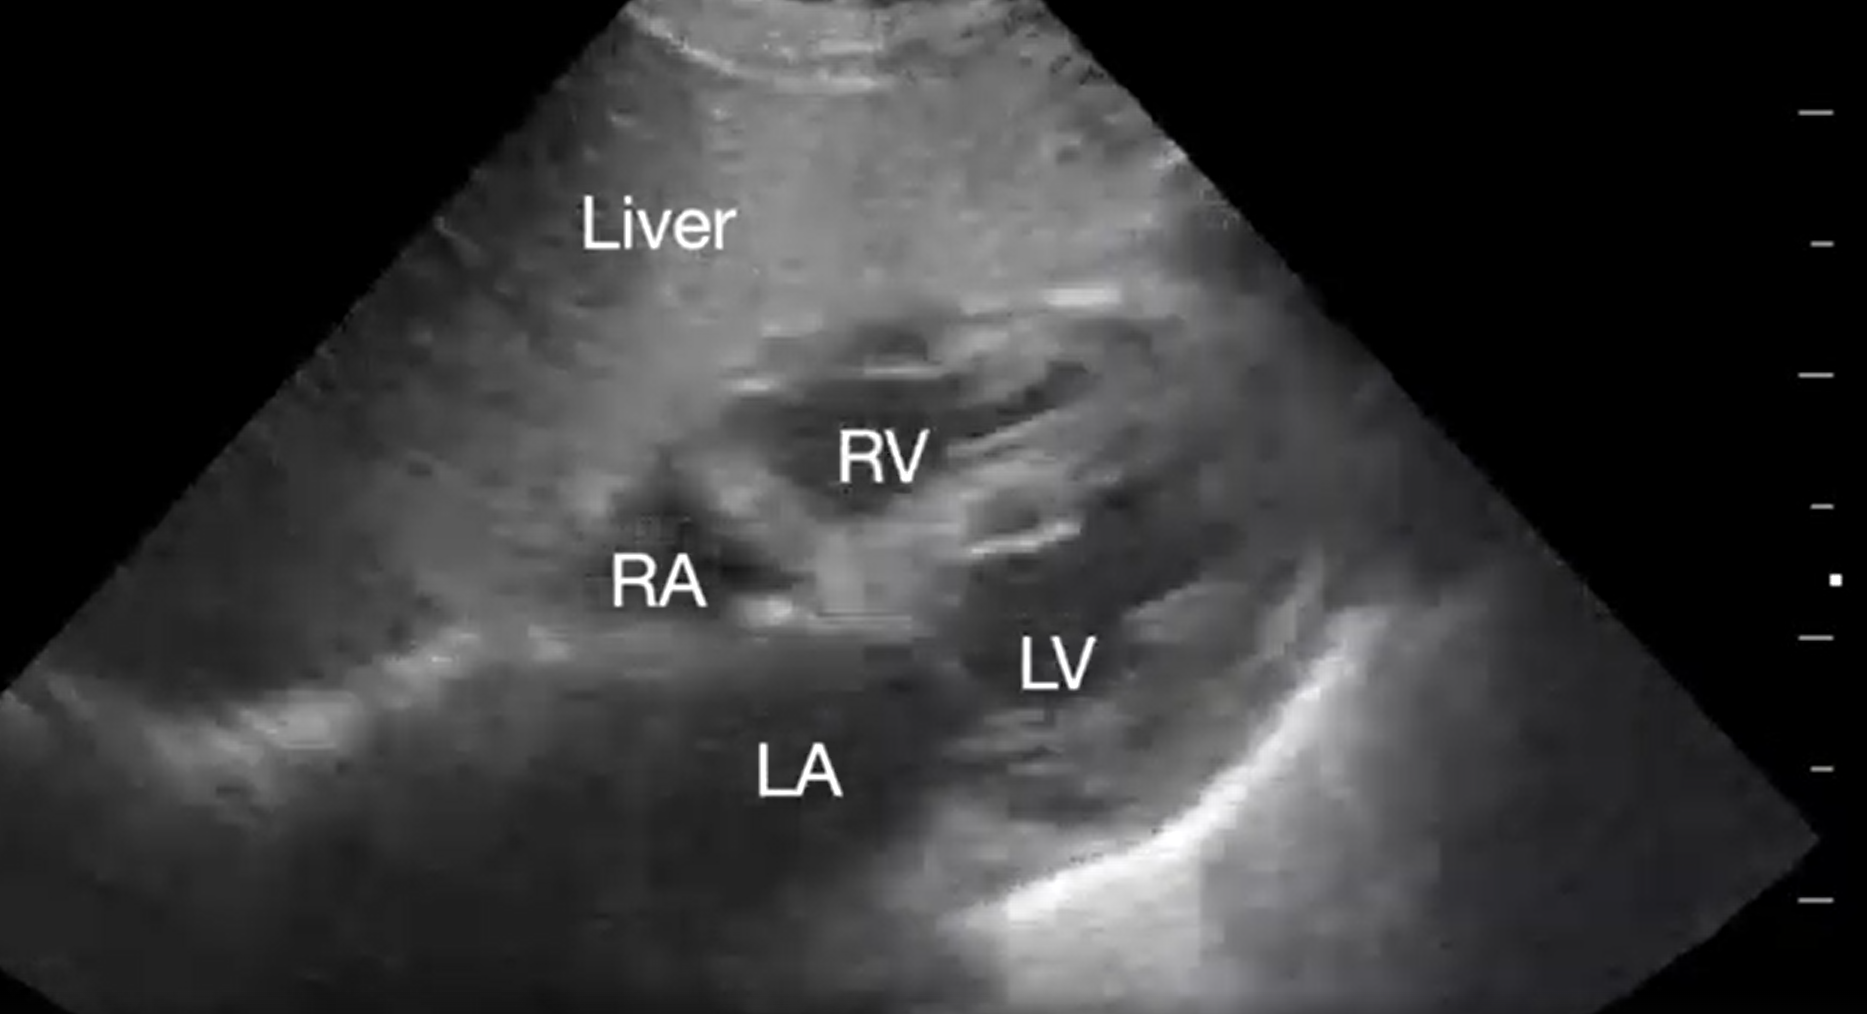

Myocardial Infarction

Myocardial ischemia is the most common cause of cardiac arrest with shockable rhythm. Presence of acute left ventricular (LV) dysfunction should raise the suspicion for acute coronary thrombosis as the cause of non-shockable PEA arrest and asystole (Video 6). Echocardiographic assessment of regional wall motion should be performed immediately after ROSC to minimize time to coronary revascularization.

Supplemental Video 6. Subcostal 4-chaber view demonstrating dilated and depressed left ventricular function. RA, right atrium; LA, left atrium; RV, right ventricle; LV, left ventricle (click to view)

The responding resident is alerted to an acutely decompensating patient in the SICU or medical or surgical ward by direct call from the primary service or by overhead Code Blue page. On arrival, the resident prepares to serve as a sonographer and complete an EASy-ALS exam. The ultrasound probe is placed in the subcostal window before the pulse/rhythm check without obstructing chest compressions. The code leader, a senior primary care team provider, is responsible for holding and resuming chest compressions. The code leader assigns a nurse to count down 10 seconds during the pulse/rhythm check; this is standard at our institution. After resumption of chest compressions, the resident interprets recorded images and communicates findings to the code leader. The primary phenotypes (Figure 2) to be identified are cardiac standstill (see Video 1), pericardial effusion (Video 2), dilated right ventricle (RV) (Video 5), dilated left ventricle (LV) (Video 6), and underfilled heart (Video 7). The resident can obtain extracardiac views (such as the subcostal IVC View, Video 3), between pulse/rhythm checks.